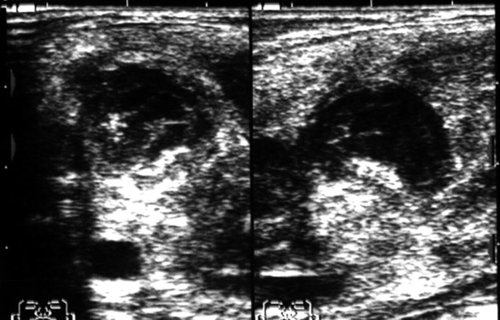

Рис. 6. Острый серозный лимфаденит с распространенным периаденитом (лимфогенный паротит, паротит Герценберга) в левой околоушной железе.

Рис. 7. Гнойный лимфаденит в околоушной железе (абсцесс околоушной железы).